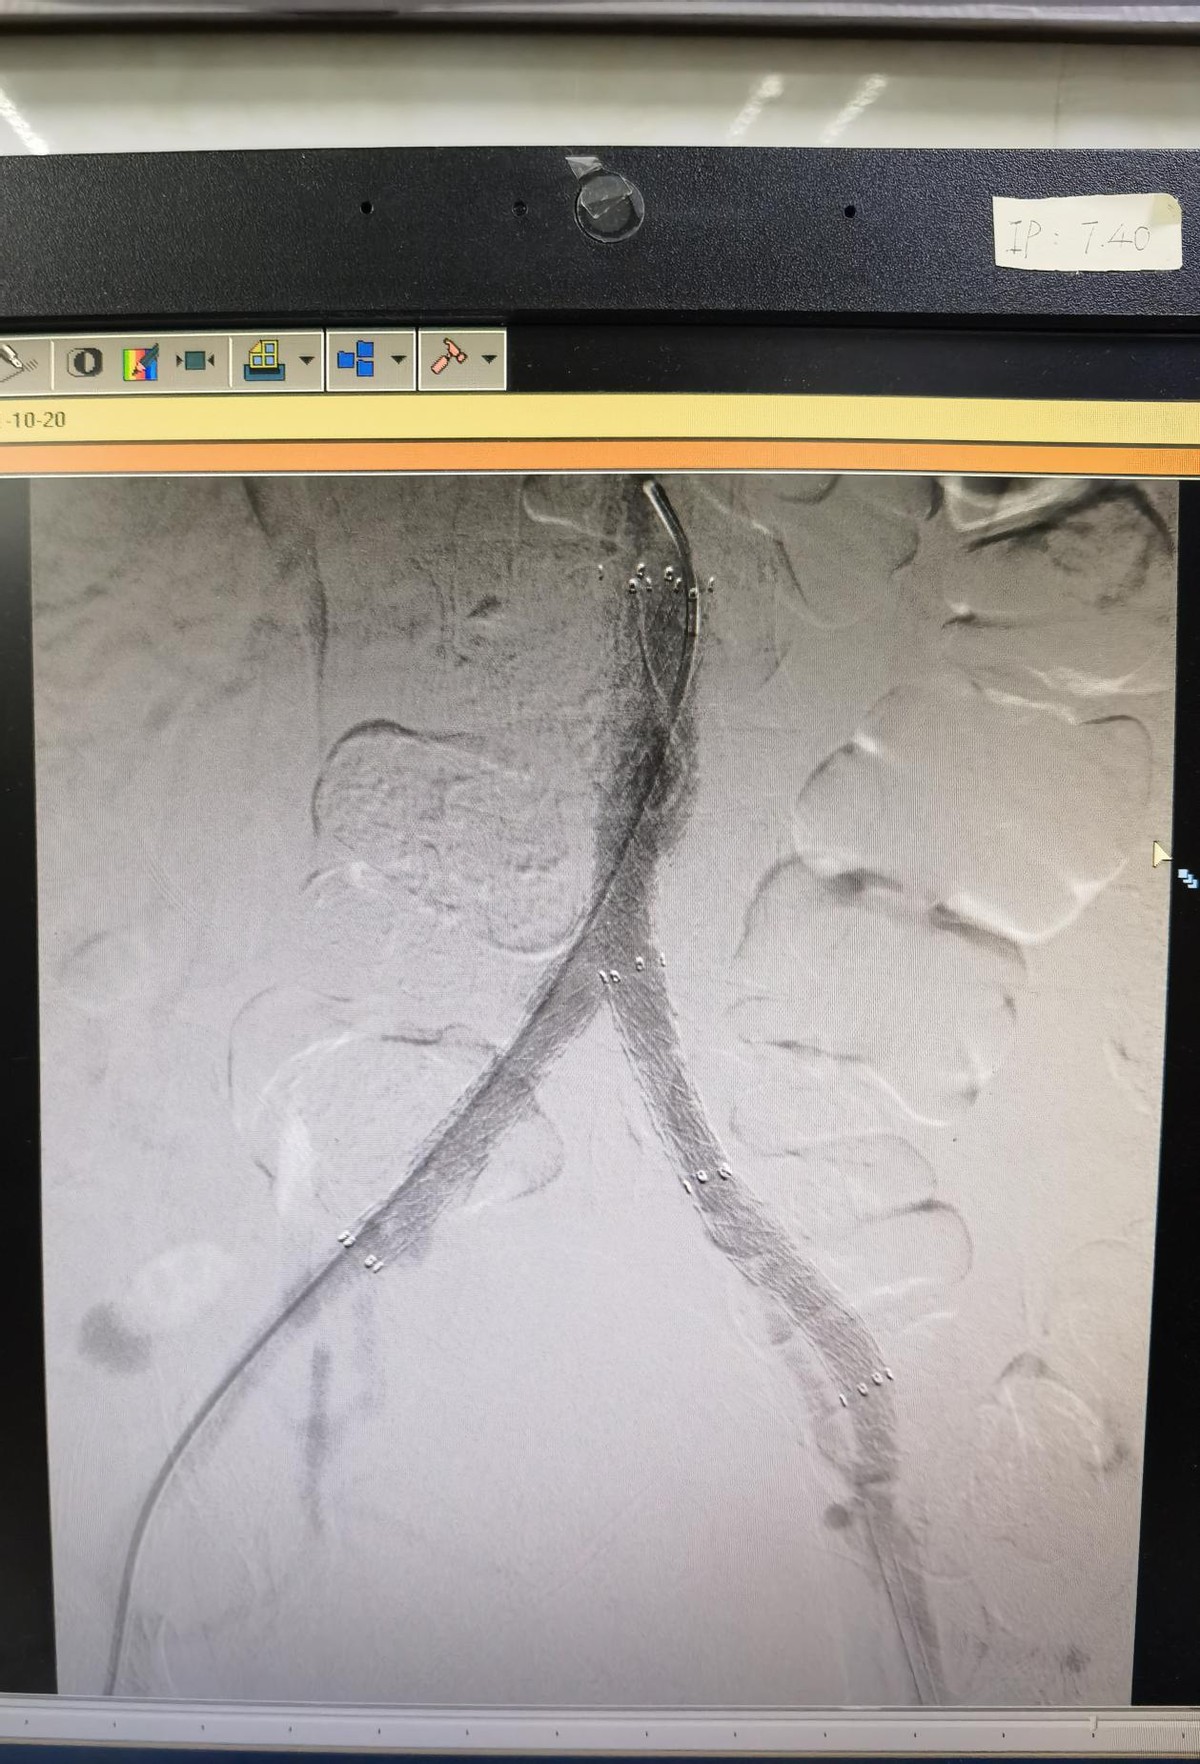

术后造影显示恢复血流的血管

5月17日下午,心脏大血管外科副主任医师唐开维与科室副主任轩永波顺利为老张完成了手术。术中造影提示老张左髂总动脉闭塞,局部多发斑块,无血流通过。腹主动脉下段狭窄约80%,右髂总动脉中上段有斑块,造成局部狭窄50- 60%,左髂总动脉起始部后闭塞。老张病情复杂,两位专家先从左侧多次尝试使导丝导管突破闭塞段,最后成功突破进入腹主动脉真腔内。考虑老张局部动脉斑块多,为预防破裂,他们进行逐级扩张,定位良好后释放支架。为处理老张腹主动脉下段狭窄的问题,他们沿左侧、右侧导丝同时送入血管支架,使用Kissing技术成功释放两枚支架。手术很成功,再次造影时显示老张体内支架位置良好,其内血流通畅,支架无明显狭窄。

介入全过程在血管造影下“直视下”下进行,虽然手术复杂,但两位专家有条不紊,手术时间短并且出血量少,不放置引流管,无切口,仅在右大腿腹股沟处留下两个小针眼。老张表示,术后感觉良好,走路也不疼了,腿脚感觉暖和了。术后又能活动自如,他开心地向大家讲述着当初奔跑在最前线的峥嵘岁月,术后4天,老张顺利康复出院了。